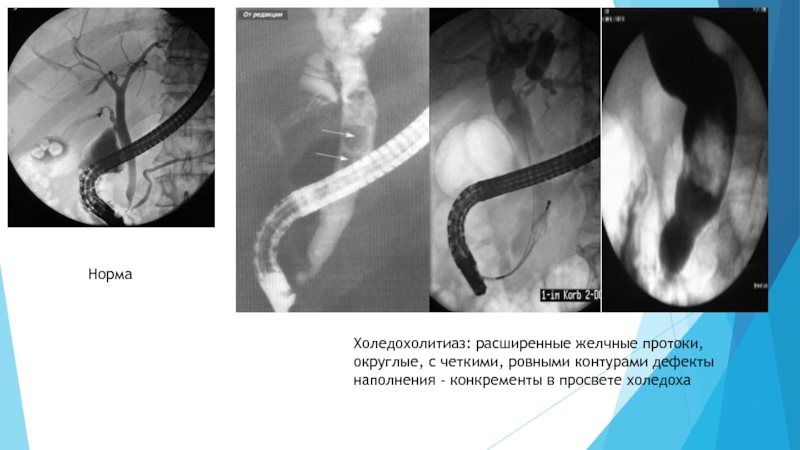

Слайд 23Признаки МХ. Холедохолитиаз характеризуется наличием одиночного или множественных просветлений в расширенных

желчных протоках на фоне контрастного вещества.. Опухоли внутри- и внепеченочных

ЖП могут полностью закрывать просвет. При проведении исследования прекращается заполнение контрастным веществом на уровне бластомотозного процесса. При незакрытом полностью протоке определяется циркулярное сужение его разной протяженности с неровными контурами и остановкой контрастного вещества в этом участке. ЭРХПГ позволяет диагностировать перихоледохеальный лимфаденит, при котором наблюдается значительное увеличение лимфатических узлов по ходу гепатодуоденальной связки вокруг общего желчного протока, что приводит к подпеченочной желтухе. При раке поджелудочной железы наблюдается сегментарное стенозирование с пристеночным расширением, равномерное сужение протока железы или полная его закупорка.

Слайд 24Холедохолитиаз: расширенные желчные протоки, округлые, с четкими, ровными контурами дефекты

наполнения - конкременты в просвете холедоха

Норма

Холедохолитиаз: расширенные желчные протоки, округлые, с четкими, ровными контурами дефекты наполнения - конкременты в просвете холедохаНорма